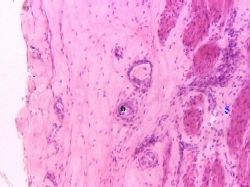

| Наружная часть стенки мочеточ- ника | а) В заключение приведём ещё один снимок мочеточника. б) На нём при большом увеличении видны мышечная (5) и адвентициальная (6) оболочки. | г) Мочеточник. Большое увеличение Полный размер |